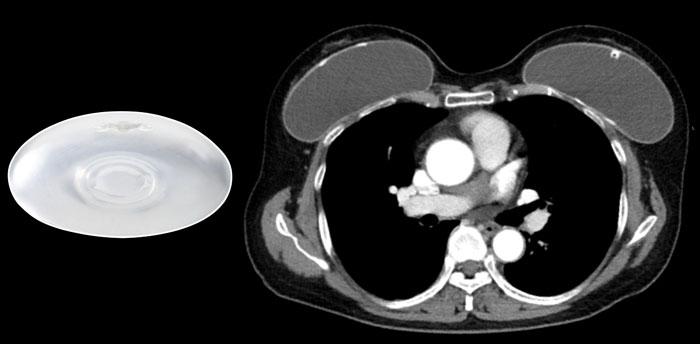

Túi độn nhân nước muối và túi độn nhân silicone được cắt đôi để thấy phần nhân có hình dạng ổn định bên trong.

Loại túi độn ngực được sử dụng phổ biến nhất bao gồm lớp vỏ ngoài bằng elastomer silicone và phần nhân bên trong là gel silicone.

Phần nhân silicone đã được cải tiến qua nhiều năm để trở thành khối có hình dạng ổn định hơn (xem hình).

Túi độn nhân nước muối

Túi độn nhân nước muối cũng có lớp vỏ ngoài bằng silicone. Chúng có thể được sử dụng chủ yếu để nâng ngực thẩm mỹ hoặc dùng làm túi giãn mô vú trong phẫu thuật tái tạo như một thiết bị tạm thời, được bơm dần bằng nước muối sinh lý. Túi độn nhân nước muối dễ bị xẹp ngay lập tức hơn khi gặp chấn thương.

Túi độn ngực có thể có hình tròn hoặc hình giải phẫu được tạo hình sẵn.

Bề mặt vỏ túi có thể nhẵn hoặc có cấu trúc nhám, bao gồm cả lớp phủ polyurethane để ngăn túi xoay.